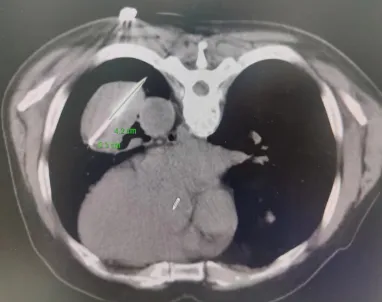

近期,我院肿瘤科裴志东主任团队为一例甲状腺癌肺转移患者成功实施了肺部病灶电冷消融术,这是我院开展的首例电冷复合消融术,手术持续120分钟,操作过程安全可控,术中术后生命体征平稳。

患者病灶位于左下肺,大小8.5*5.6cm,患者俯卧位CT扫描定位,左下肺可见肿块影,局部麻醉后,按照手术设计穿刺路径,分别将阳极针、阴极针经皮穿刺进入病灶,通过冷消融4个循环、电解消融1个循环后,CT扫描可见肺内病灶坏死明显,手术2小时后顺利结束。术后病人无不适症状,3天后好转出院。